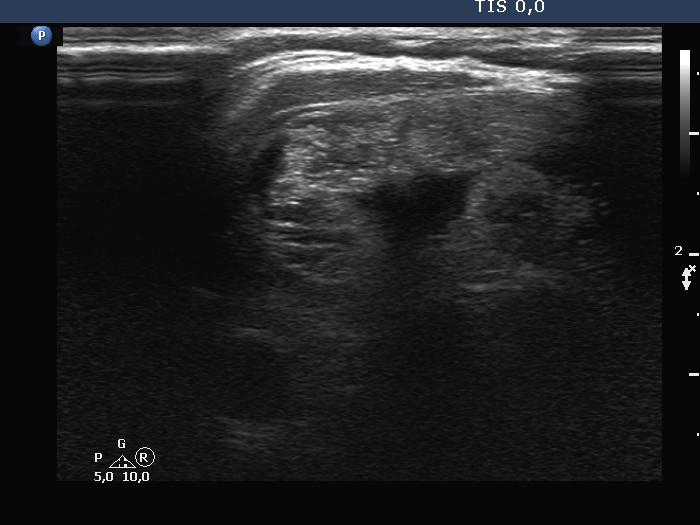

Follow-up investigation 6 years later (ultrasonographic picture 6)

Right lobe, longitudinal scan